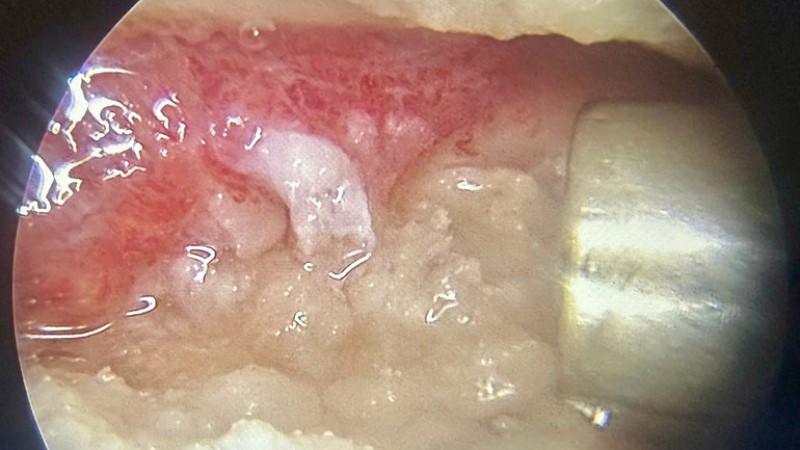

Các bác sĩ đã tiến hành nội soi cắt lọc, làm sạch khớp, đồng thời kết hợp ứng dụng keo Fibrin tự thân giàu tiểu cầu Platelet Rich Fibrin (PRF)-đây là một loại keo tự thân được chiết tách từ chính máu của bệnh nhân.

Phẫu thuật nội soi cắt lọc khớp gối và bơm PRF.

Từ 240ml máu ngoại vi của người bệnh, bác sĩ tách chiết được 10,9ml PRF, sau đó bơm trực tiếp vào các vị trí tổn thương trong quá trình nội soi cả hai khớp gối.